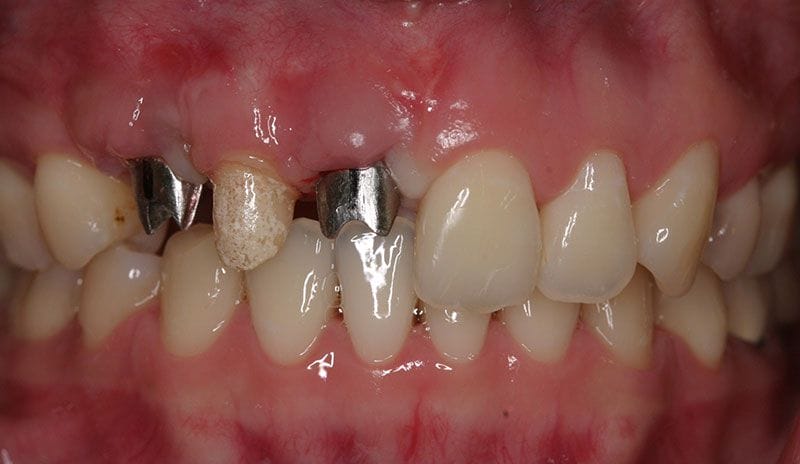

陳小姐是一位美貌與才氣兼具的事業女強人,在一次晚宴中,已經做了十多年的門牙假牙脫落,陳小姐緊急求助黃醫師,立刻進行"立即式植牙" ,將已經蛀壞的牙根拔除,植入人工牙根,再做上美觀的假牙,讓陳小姐無後顧之憂的面對明日的工作。

植牙過程